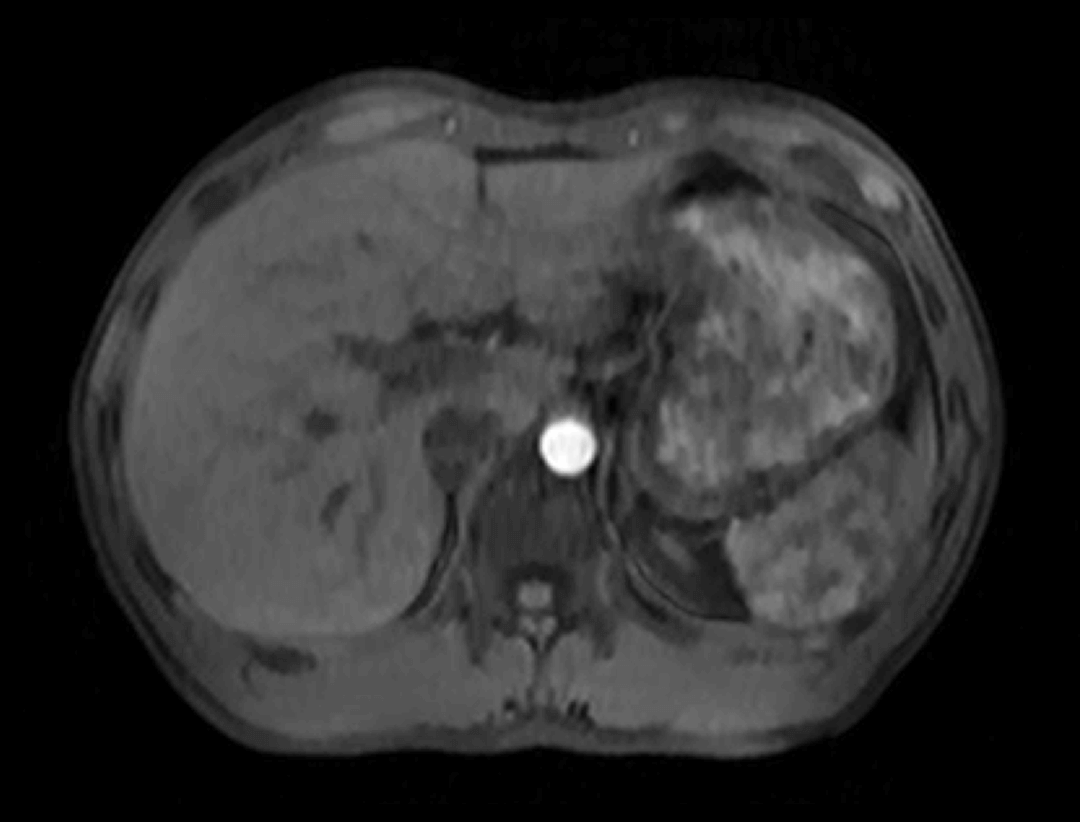

光梭®2.0成像应用

光梭®2.0成像应用于磁共振腹部动态增强扫描,可实现16倍采集加速,清晰捕捉组织信号连续动态变化,精准捕获腹部动态影像的每一瞬间,实时、全方位锁定病灶。